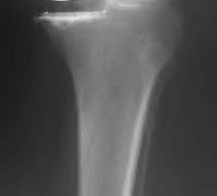

The radiograph demonstrates a periprosthetic femur fracture extending to the tip of the stem. The long spiral fracture is consistent with a loose implant. The bone stock is sufficient. Therefore, this fracture pattern would classify as a B2 using the Vancouver classification system. The Vancouver classification for periprosthetic femoral fractures is simple yet incorporates all the pertinent factors such a location, stem fixation, and bone stock. Type A is a trochanteric fracture- lesser or greater. These can be treated non-operatively usually and ORIF if symptomatic. Type B fractures are around or just below the stem and are subdivided into three types. Type B1 is a fracture with a well fixed stem.

The treatment is cable plating or allograft struts or a combination of the two. Type B2 is a fracture with a loose stem with good bone stock. The treatment is a cementless porous coated long stem atleast two diameter length past the

fracture site. Type B3 is a fracture with a loose stem and comminution. For younger patients, use cementless porous coated long stems with allograft struts. For older patients, consider a tumor prosthesis. Cement fixation is sometimes necessary Type C is a fracture well below the stem tip. These can be treated independently of the prosthesis.